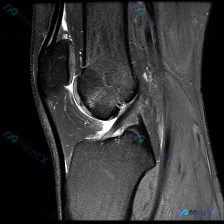

看到这张膝关节MRI矢状位T2序列的影像,整理一下分析思路,和大家一起讨论。 先整理影像核心发现 这是单张膝关节MRI矢状位T2序列影像,核心异常如下: 1. 骨骼结构:股骨远端、胫骨近端、髌骨轮廓完整,无明显骨皮质断裂 2. 韧带:前交叉韧带(ACL)走行可见,但近股骨附着点和中段低信号连续性不佳...